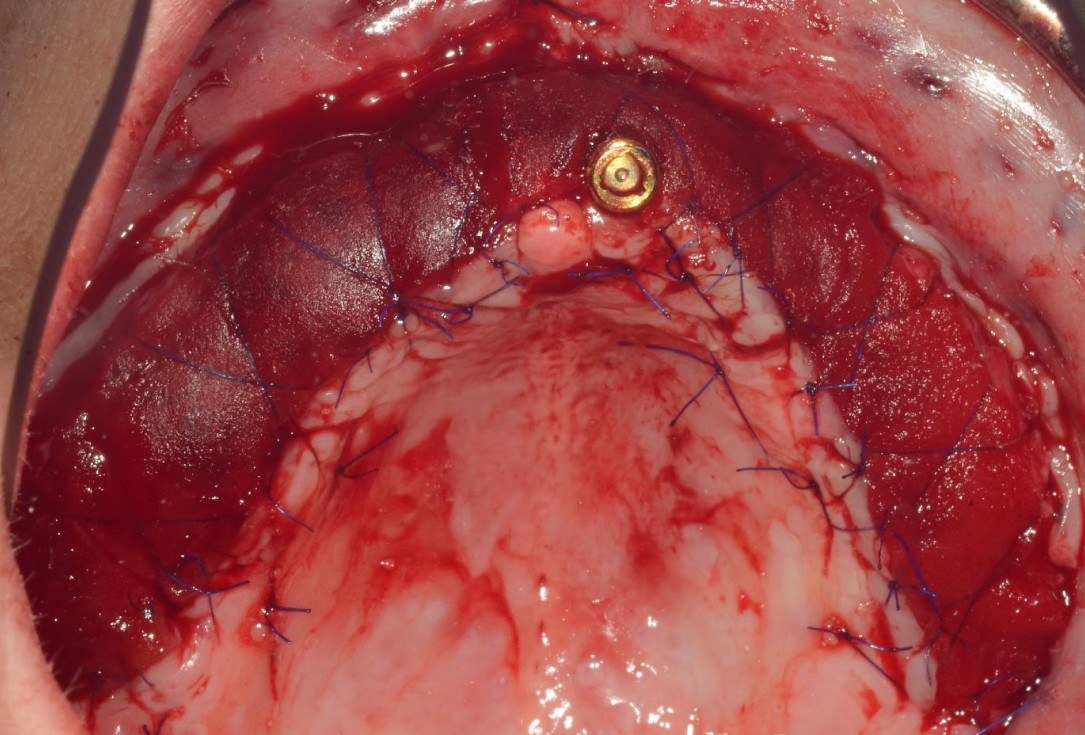

2/8 - Split-flap preparation with intact periosteal layer and apical fixation of the buccal flapmucoderm® for full arch reconstruction of insufficient vestibular depth and lack of keratinized tissues - Dr. B. Mólnar & Prof. P. Windisch

3/8 - mucoderm® fixation with single and cross-suturesmucoderm® for full arch reconstruction of insufficient vestibular depth and lack of keratinized tissues - Dr. B. Mólnar & Prof. P. Windisch

4/8 - mucoderm® fixation with single- and cross-suturesmucoderm® for full arch reconstruction of insufficient vestibular depth and lack of keratinized tissues - Dr. B. Mólnar & Prof. P. Windisch